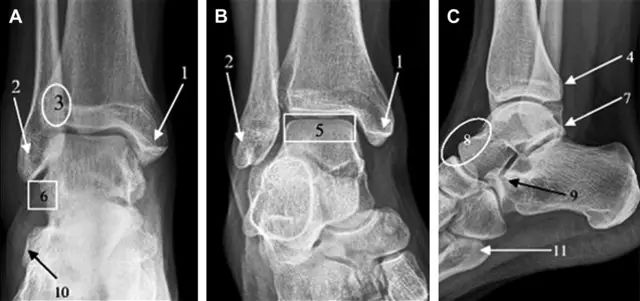

急诊科医生常遇到的一个问题是:踝关节疼痛。对于这类患者,想要分辨是否存在骨折,X 线检查是主要手段。然而,由于各种原因,有些踝部骨折非常容易漏诊。

首先,来看踝关节骨折的高危区(图 1)。

图 1 踝部探查模板。阅片时,需对踝关节的前后位片(A)、内旋转位片(B)侧位片(C)仔细阅读,逐一详细排查。上图中的骨折:1. 内踝骨折,2. 外踝骨折,3. 胫骨结节骨折,4. 胫骨后踝骨折,5. 距骨骨软骨骨折,6. 距骨外侧突骨折,7. 距骨后突骨折,8. 距骨舟骨关节背侧骨折,9. 跟骨前突骨折,10. 跟骨骨折嵌插入趾短伸肌,11. 第五跖骨底骨折

涉及到三角韧带和外侧副韧带(LCL)的复杂性骨折常常不难发现,尤其是存在表面软组织肿胀时。然而,后胫腓韧带牵拉引起的胫骨后踝骨折则很难发现。这些骨折大小不一(图 2),却很重要,因为他们常与胫骨远端螺旋骨折有关,或者是三踝骨折的一部分。

图 2 胫骨后踝骨折。A 侧位片示来源于胫骨后踝的一个小骨折碎片(箭头),因踝部扭伤导致;B 另一位跖屈损伤的患者,侧位片示一个大骨折块(箭头)

Tillaux 骨折,是足外旋外展时,胫腓前韧带牵拉引起的一种胫骨结节撕脱性骨折。斜位片上可见典型表现(图 3)。

图 3 摔倒后胫骨结节骨折。A 正位片示一细小斜型骨折线(箭头);B 侧位片示正常;C 冠状位 CT 三维成像更清晰地显示了骨折线和骨折块大小(空箭头);D 矢状位 CT 多维重建图像示骨折位置(箭头)

距骨外侧突骨折常因踝外翻背屈时,跟骨上外侧面撞击距骨外侧突下缘导致,或偶尔由踝内翻引起,被称为「滑雪板者骨折」。这种骨折只能在踝关节正位片上发现,而且外踝远端表面软组织肿胀往往是一个重要线索(图 4)。

图 4 距骨外侧突骨折。A 正位片示内翻损伤所致的距骨外侧突撕脱性骨折(箭头);B 另一位患者,踝外翻损伤导致典型的「滑雪板者骨折」,X 片上可见一较大的三角形骨折块(方框);C 第二位患者的 MRI 矢状位 T1 加权像示横行骨折(箭头)

距骨后突有内侧结节和外侧结节,距骨后突内侧结节撕脱性骨折常发生在背屈内旋的暴力作用下。严重跖屈时,胫骨后缘和跟骨挤压距骨后突外侧结节呈楔形,易发生粉碎性骨折。这些骨折细微且需与三角骨鉴别。侧位片观察距骨后突骨折最佳,常规拍片很难发现,当高度怀疑这种骨折又没法做 CT 时,建议加做多个角度的外旋斜位片(图 5)。

图 5 距骨后突骨折。侧位片(A)和 MRI 矢状位 T1 加权像(B)均示后外侧突的简单骨折(箭头),再次阅片时才发现 X 线片上的骨折;侧位片(C)和 CT 横断面图像示后内侧突的粉碎型骨折(箭头)

呈 Y 形的分歧韧带附着于跟骨前突上,是维持踝关节跖屈和背屈稳定性的重要结构。跟骨前突骨折常发生于足跖屈内旋、分歧韧带被牵拉时,或者足背屈外旋、骰骨和距骨挤压前突时。而这些骨折在初次 X 线检查时常常被漏诊掉。踝部侧位片诊断这些骨折最佳,准确诊断的关键点在于,必须仔细查看是否存在骨皮质中断(图 6)。如果侧位片可疑,建议加做斜位片协助诊断。

图 6 跟骨前突骨折。A 侧位片示跟骨前突骨折(箭头),与舟骨的重叠使骨折显示模糊;B 另一位患者的侧位片示内翻损伤所致的骨折(箭头),这种损伤机制引起小块的骨折

另一种重要的跟骨撕脱性骨折,于足内翻时发生在趾短伸肌的起点处。观察来自跟骨背外侧的、不同大小的骨折块,前后位 X 片最适合不过了(图 7)。

图 7 溜冰受伤的患者,趾短伸肌跟骨撕脱性骨折。正位片示 2 个骨折块(箭头)来源于跟骨前外侧、趾短伸肌的起点处。踝关节外侧远端是否存在软组织水肿是一个重点观察点